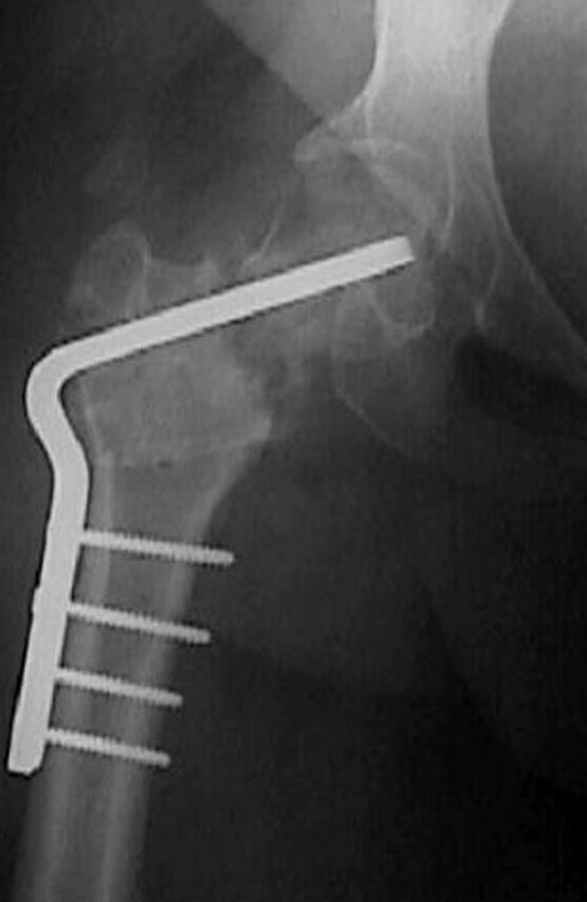

Несколько снимков из моей коллекции, чтобы разьяснить, почему мы до сих пор делаем различные варианты остеотомии.

На рисунке N1 предоперационный план лечения ложного сустава шейки бедра- линия ложного сустава, угол и направление введения импланта, клиновидная остеотомия в градусах и миллиметрах, второй снимок после коррекции, расчет, на сколько удлиняется конечность и размеры импланта;

N3 рисунок окончательный снимок, после операции моя рентгенограмма должен выглядеть примерно как эта картина. На N4 снимке клин перед удалением; N5 послеоперации 3 нед.; N6 окончательная рентгенограмма.

(доложен в Ст. Петербурге 2003 и в Москве 2004)

варус при проксимальном отделе 95 градусной пластиной.